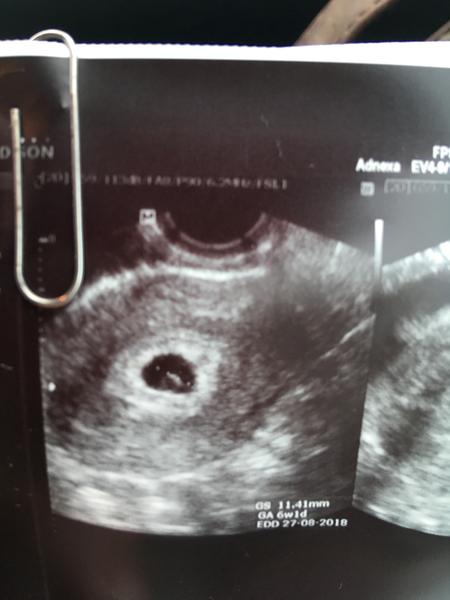

@pipinka Ahoj,ted jsem se vratila od doktorky.Preddtav si,ze je vse v poradku a mimi krasne vyrostlo!😍Od ctvrtka je gestacni vacek 11,4mm a uz byl videt i zloutkovy vacek.Takze uz tam je i embryo.Ufff!To byly nervy.Hematom nikde neni,jen trosku asi 2mm srazeninka,ale to pry nestoji za rec.Pry mam asi krehci cevy.Tak tuk tuk,zatim vse v poradku.Spineni dnes zatim temer vubec.